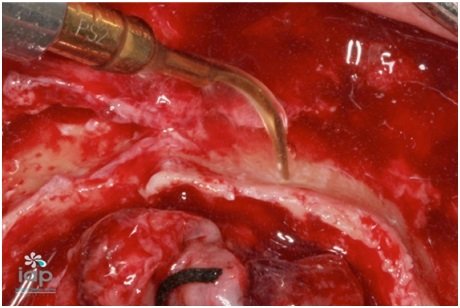

Após conversar e analisar as opções de tratamento, optou-se pelo uso do rhBMP-2 (Infuse Bone Graft, 5,6 cc, Medtronic Sofamor Danek USA, Inc), associado ao beta tricálcio fosfato (Bone Ceramic, partículas 500- 1.000 micrometros, Straumann, Basel, Suíça) e telas de titanio (Titanium Augmentation Micro Mesh – 120 x 60mm e parafusos,Ace Surgical Supply Co.,Inc)